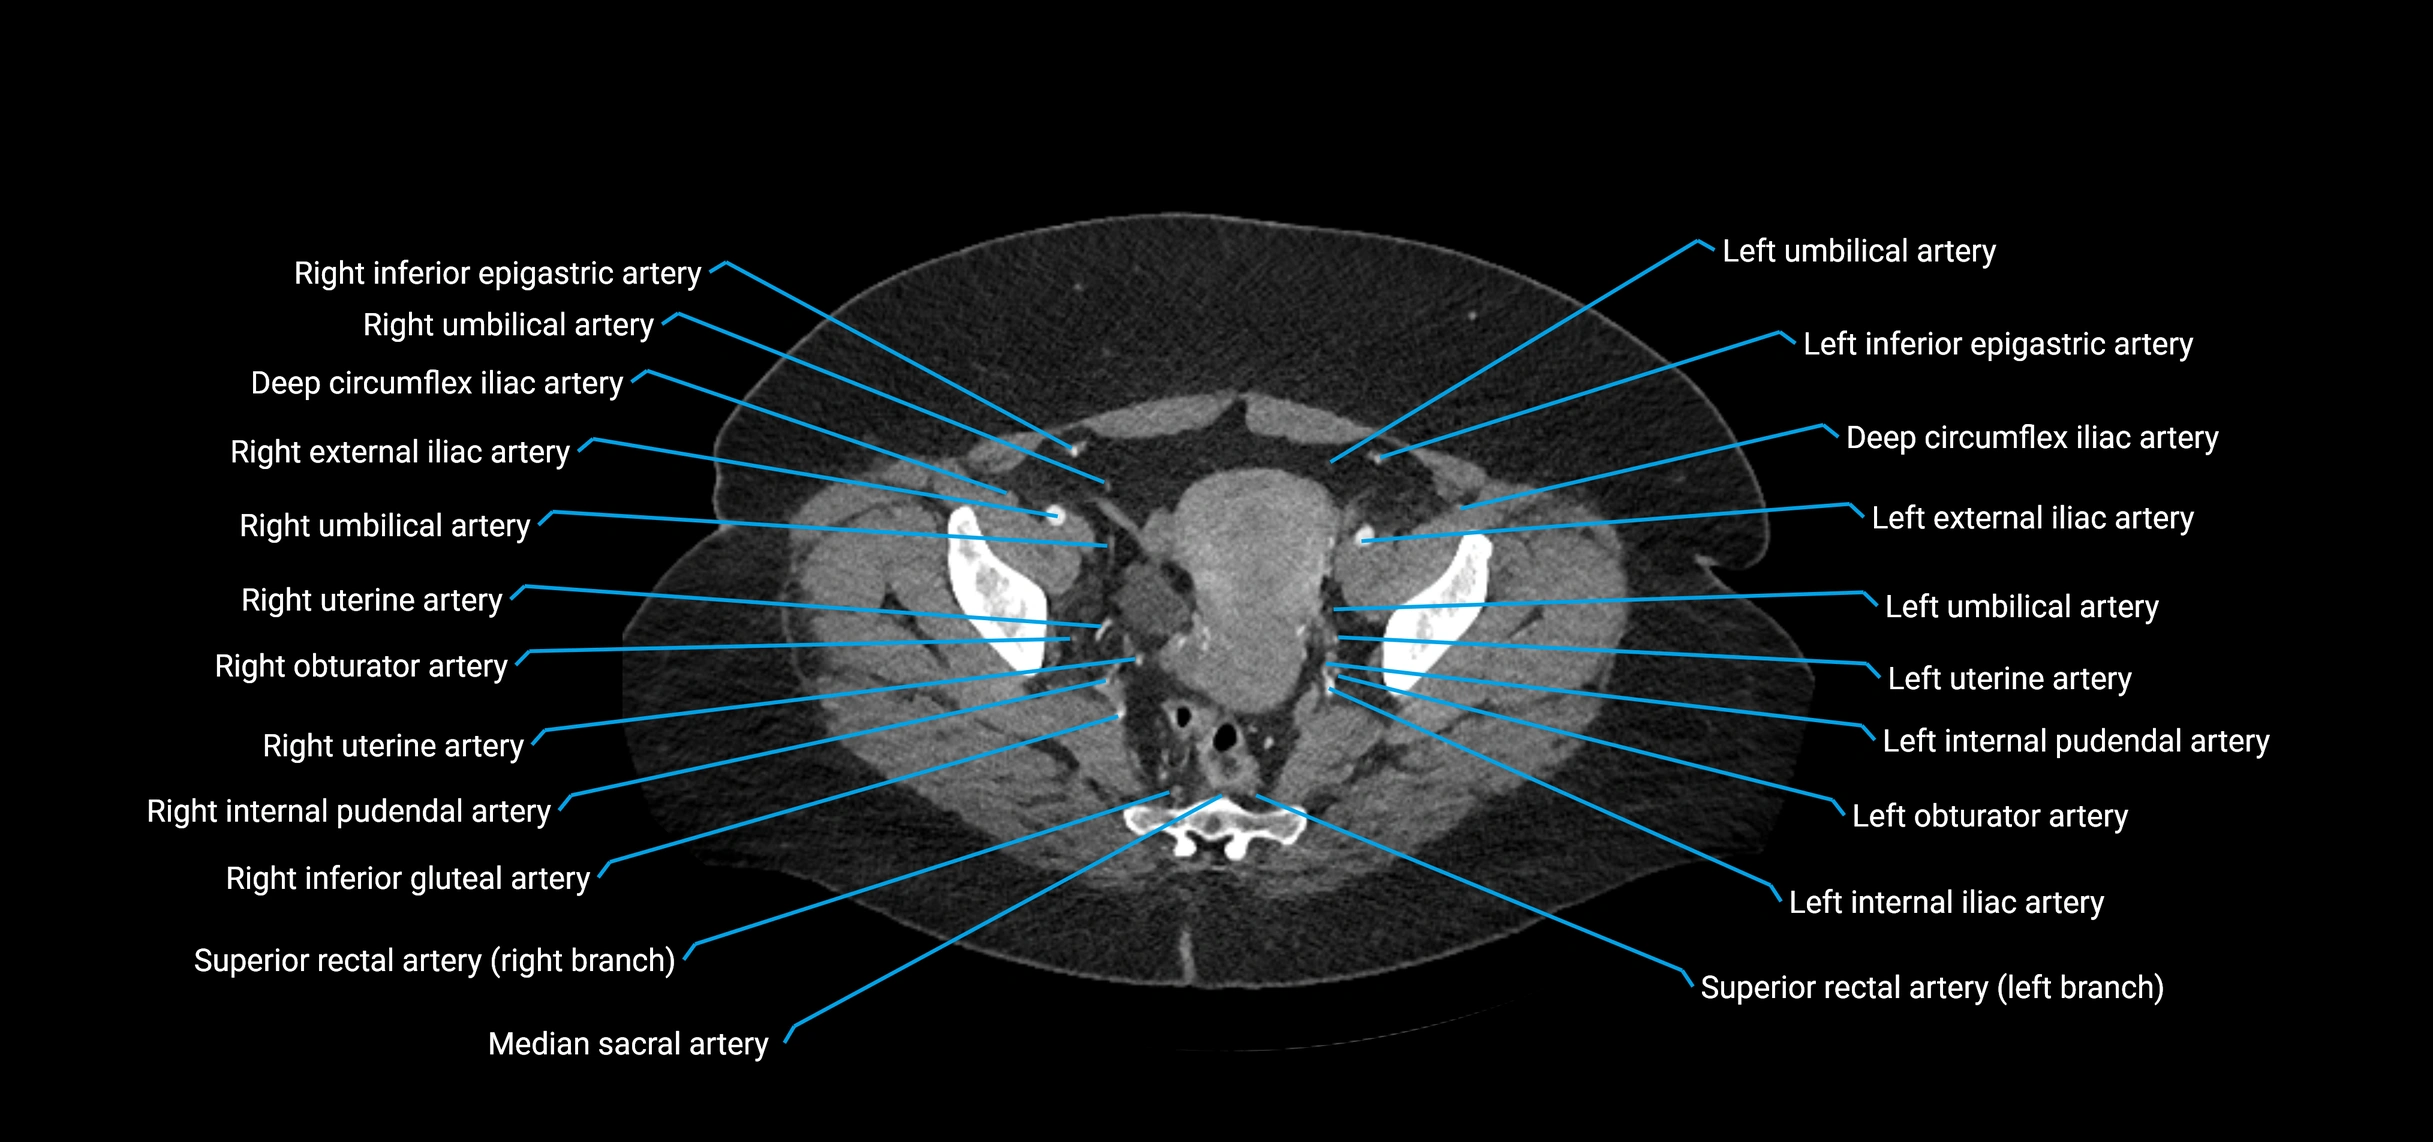

CT images

image

Contrast-enhanced CT (CTA):

• Gold standard for abdominal aortic imaging

• Provides excellent detail of lumen, wall, aneurysm, thrombus, and branch vessels

• Multiplanar and 3D reconstructions help in aneurysm measurement, stent graft planning, and dissection evaluation